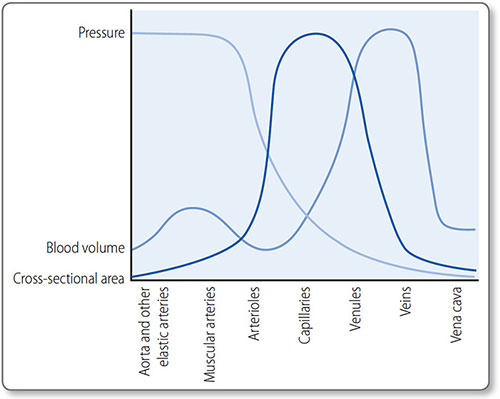

VESSELS

Ventricular contraction forces blood through the arteries under high pressure. As arteries branch, the number of blood vessels increases but their individual calibre decreases. Vast networks of capillaries perfuse tissues, in which substances are exchanged between blood and cells. Veins return blood to the heart under low pressure.

Types

The structure of each vessel type reflects its function (Table 1.2).

Elastic arteries

These are the major proximal arteries: the aorta and the brachiocephalic, carotid, subclavian, iliac and pulmonary arteries. Their tunica media contain many elastic fibers, which convert the intermittent, pulsatile blood flow from heart contraction into the continuous flow allowing constant tissue perfusion. They absorb energy during systole and discharge it in diastole.

Muscular arteries

Muscular – or distributing arteries – distribute blood to the resistance arterioles. They have multiple layers of smooth muscle in their tunica media, and include the radial, mesenteric and femoral arteries.

Arterioles

Arterioles are known as resistance vessels because they regulate systemic vascular resistance (Figure 1.13). They contain one or two layers of smooth muscle that are autoregulating and affected by neuroendocrine control (see page 49).

Arteriolar muscular tone is the primary controller of perfusion as these vessels supply capillary beds.

Capillaries

Capillaries consist of a single endothelial cell layer. They are 5−20 μm in diameter and about 1 mm long. However, they have a very large combined cross-sectional area, which results in a slow transit time. Known as exchange vessels, they are the site of gas, nutrient and waste product exchange between blood and tissues.

Figure 1.13: Pressure, blood volume and surface area at each level of circulation. The largest pressure drop occurs at the resistance vessels (arterioles), capillaries have the largest surface area and veins (capacitance vessels) hold the most volume.

Venules and veins

Post-capillary venules join to form larger venules, which join to form veins.

Venules and veins have a much thinner tunica media and less smooth muscle than arteries and arterioles. They are thin, compliant and lack elastic recoil. Consequently, they accommodate large increases in blood volume with minimal increase in pressure. The large combined cross-sectional area means resistance is low, so their low pressures are sufficient to return blood to the heart.

The large capacity of veins acts as a reservoir of blood and is regulated by the ANS. Sympathetic activation, for example, results in venous constriction, increasing venous return (and central venous pressure). Venous return is aided by the skeletalmuscle pump, where skeletal muscular contraction forces blood toward the heart and venous valves prevent backflow.